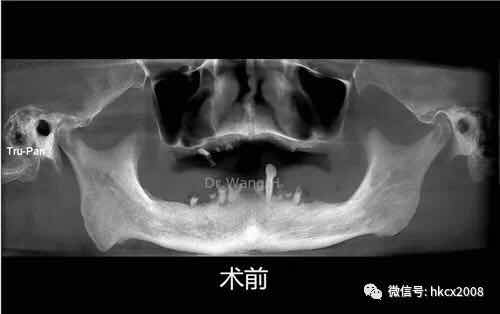

说这番话的是,来自福建的张老师,在杭州口腔医院城西院区特需专家科王辉主任团队402诊室顺利完成全口种植牙修复。